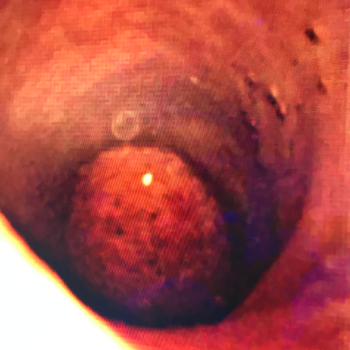

Si tienes cálculos o piedras en la vesícula biliar, debes operarte para evitar complicaciones como colecistitis o inflamación y

dolor de la vesícula, perforación de la vesícula, obstrucción de los conductos biliares por cálculos, pancreatitis y cáncer de vesícula.